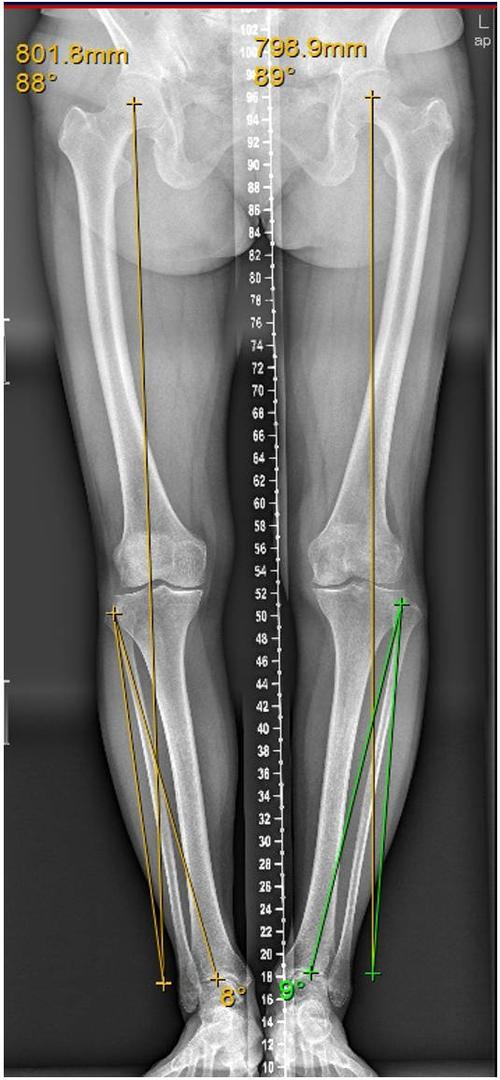

膝关节力线,膝关节力线图

75对于膝内翻,这条直线偏于膝关节中心点的内侧(图②);75如果正常

膝关节力线图

下肢力线

下肢力线图

下肢力线示意图

正常下肢力线示意图